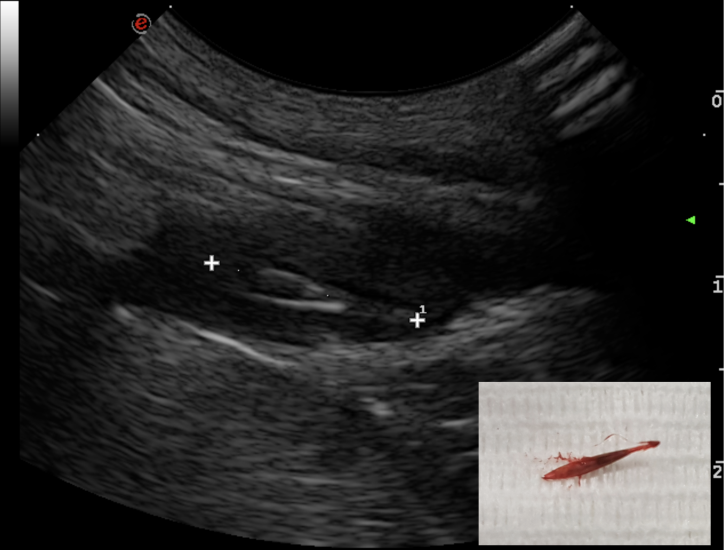

The use of ultrasound for the detection of such foreign bodies is well known and their ultrasonographic features have been widely discussed. Grass awns ‘appear as linear spindle-shaped hyperechoic structures of variable length, with two or three parallel reflecting interfaces corresponding to the seeds and seed covers. Often an anechoic halo due to the accumulation of fluid is present around the foreign body, which sometimes improves interface visualisation’.

Four dogs referred for recurrent abscess in the lumbar region have been seen at the hospital between October 2018 to January 2019. A migrating vegetal foreign body was identified in each dog with the use of ultrasonography. All retrieval procedures were performed in the sonography suite with the patient under general anaesthesia. The region of interest was aseptically prepared and a small stab incision with a #11 scalpel was performed approx. 2 cm cranial to the foreign body, with the plant awn imaged in sagittal section. A Hartmann forceps was inserted through the skin incision and directed toward the tip of the foreign body under ultrasonographic guidance. The forceps were opened and the foreign body grasped and withdrawn. The shape of the foreign body was compared with the sonographic images and the site of the abscess was re-scanned to determine potential residual foreign bodies or fragments. In all dogs, the abscess was flushed with saline and oral antibiotic therapy was administered for 7–10 days. The duration of the procedure ranged from 20 to 40 minutes. Suture of the skin incision was not necessary.

but another abscess occurred 1 month later.

surgical exploration – nothing found. Abscess reoccurred within a few weeks and antibiotics prescribed until

late January. Referred in February 2019